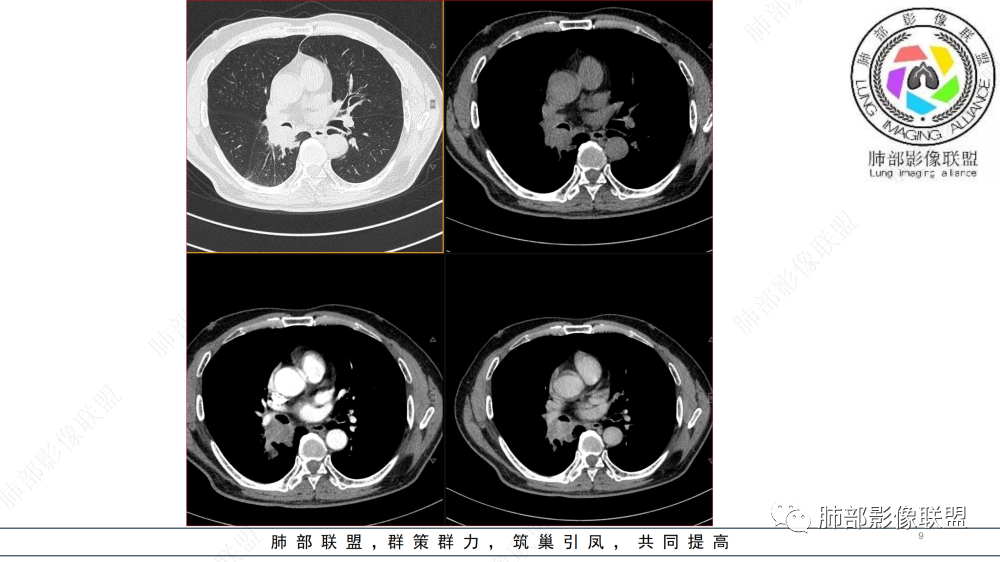

晨读 右肺中间段支气管至下叶支气管部分狭窄及堵塞,管壁偏侧增厚腔内外侵犯,软组织肿块形成,远侧肺内阻塞性炎症。考虑恶性病变,鳞癌,类癌可能

中年男性,痰中带血,病史半年,一直没有发热,感染指标不高,胸部CT右侧肺门不规则肿块影,边缘清楚,棘状突起,浅分叶,血管集支束,空泡征,不均匀强化,右肺斜裂结节状增厚,右侧中间支气管外压改变,右肺下叶背段支气管截断,无明显淋巴结肿大,恶性是没有问题,至于类型病灶大无坏死空洞,鳞癌靠后,无明显淋巴结肿大,小细胞靠后,所以腺癌首选。

晨读 右肺中间段支气管至下叶支气管狹窄,腔内见软组织肿块,腔内外侵犯,右下肺门软组织肿块形成,不均匀强化,冠状位病变纵径大于横径,远侧肺内阻塞性炎症。定性恶性,考虑腺样囊腺癌或鳞癌

晨读病例,中年男性,咳嗽咳痰半年,有痰中带血,影像表现右肺下叶支气管腔内外占位,形态欠规则,有冰山征表现,支气管截断,有强化,考虑恶性病变,类癌或鳞癌可能,鉴别腺癌、粘液表皮癌等。

右肺下叶肺门区肿块,向中间段支气管突出,下叶支气管阻塞狭窄,腔内外侵犯,不均匀强化,内可见低密度,冠状位病变沿支气管走行生长,远侧肺内阻塞性炎症,考虑鳞癌,鉴别类癌

中老年男性,右肺下叶背段支气管内新生物,近端可见息肉样突起,远端沿分支支气管生长堵塞,肺门口病灶增强后明显强化,峰值达140hu,远端部分强化不明显考虑粘液栓,考虑典型类癌,鉴别鳞癌。

右肺叶中间段支气管见软组织影不完全阻塞及管腔变窄,向管腔外突破,向下叶背段浸润性生长,见指套及息肉样特点,不均匀明显强化,右肺下叶背段少许阻塞性炎症,肯定恶性肿瘤,小细胞Ca首先,支气管疾病谱恶性肿瘤:类癌,鳞癌,囊腺癌,粘液表皮样癌,与鳞癌,囊腺癌鉴别,支气管镜取材活检可以明确诊断。

晨读,右肺中间段及下叶支气管管腔占位,向管腔内突入,浸润性生长,支气管近端截断,周围少许阻塞性炎症,增强后轻度强化,考虑类癌,腺样囊性癌

右肺中间段及下叶支气管腔内外生长肿块,远端未见明显阻塞改变,不均匀渐进强化,考虑腺样囊性癌或类癌

晨读:男,57,咳嗽半年,痰中带血3天。胸部CT:右中间段支气管到下叶支气管堵塞性狭窄,管腔内见软组织肿块,壁内外侵犯,长轴沿气道延展,下叶基底多段累及,病变纵径大于横径,远侧可见索条、阻塞性炎症。考虑恶性,腺样囊腺癌?鳞?鉴别N内分泌类、炎性肉芽肿等

气管截断,血管破坏,跨壁内外生长,阻塞性炎症,定性恶性,明显强化,首先考虑类癌,鉴别鳞癌